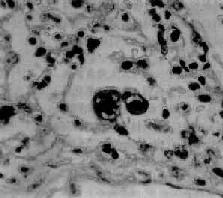

图9-15 大叶性肺炎

肺泡腔内充满纤维素性渗出物,纤维素丝穿过肺泡间孔,使相邻肺泡内的纤维素网互相连接